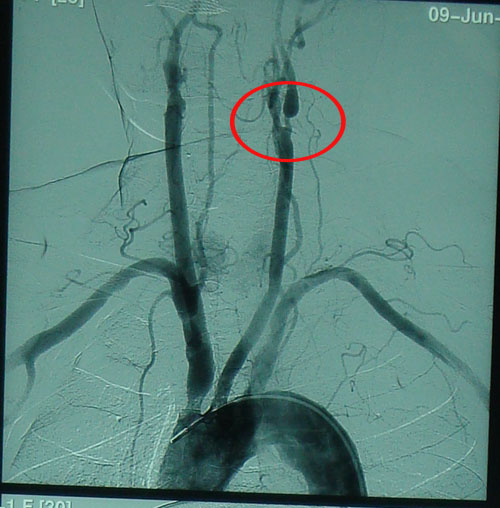

DSA:全身动脉多发粥样硬化,左侧髂内动脉闭塞,右侧颈内动脉起始部狭窄约50%,左侧颈内动脉起始部狭窄约90%。

本例患者左侧颈内动脉严重狭窄达90%,但其症状仅表现为反复发作性头晕,未出现严重的中风发作,因此为预防中风发作,应行CEA取出斑块,彻底去除病变。 2009年6月25日,协作组张勤奕教授在北京大学人民医院为其成功实施了左侧颈内动脉内膜剥脱术。术后患者恢复很好。